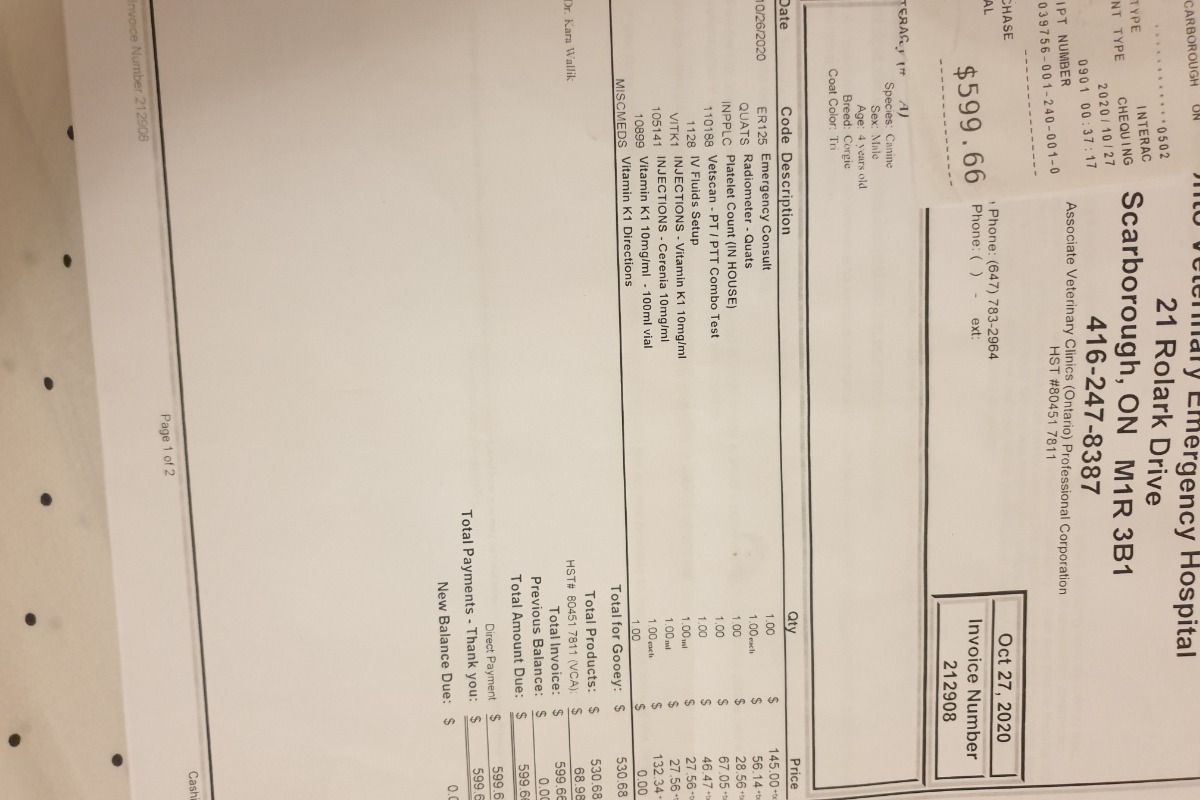

Gooey, Male.Gooey has been my best friend for 4 years, I got him since he was still a 3.5mths puppy, I brought him with me on the plane from Indonesia. While it is also the first time with me arriving in Canada. We going through a lot of difficulties together, while this pandemic also make everything more difficult for us. Right now his vet bills totalled $3401.

I have peoples donated to me directly totalled $1120. So I just need a little bit more kindness from all of you, please.